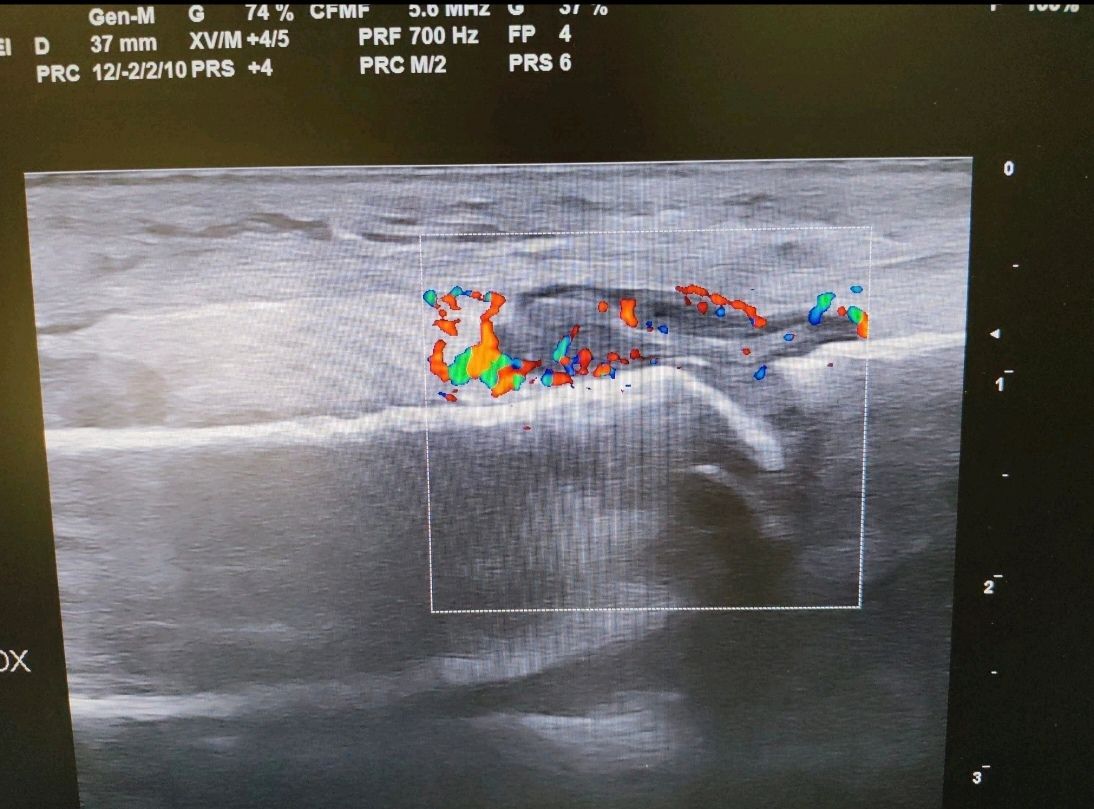

Nel mio percorso formativo ho conseguito esperienza nell'ecograifa articolare, nelle infiltrazioni articolari, nelle biopsie sinoviali e nella gestione delle terapie immunosoppressive con farmaci biotecnologici

• Ecografia osteoarticolare

67 € - 180 €